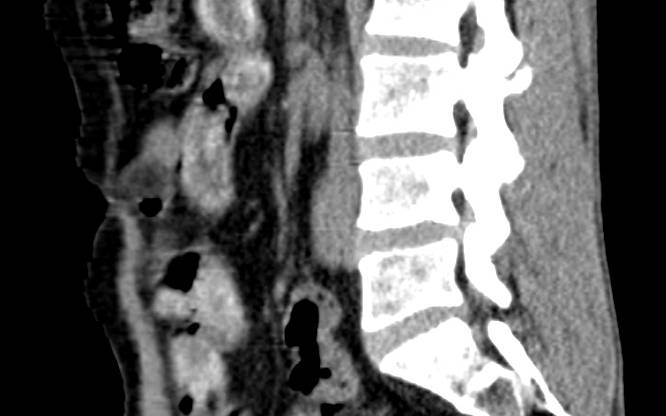

Nach der Kontrolle wurde der Mann zur weiteren Untersuchung ins Krankenhaus gebracht. Dort bestätigte ein Röntgenbild den Verdacht: Der Schmuggler hatte seinen Bauch mit insgesamt 75 sogenannten Bodypacks gefüllt. In den Drogenpäckchen befanden sich 450 Gramm Kokain und 300 Gramm Heroin - mit einem Straßenverkaufswert von fast 50.000 Euro.